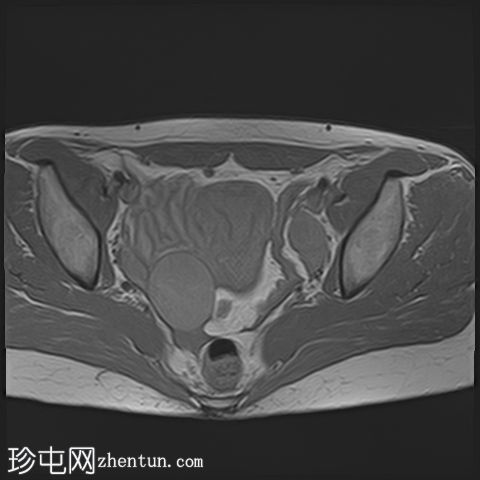

轴向

T2

已确诊3例卵巢囊肿:

右侧卵巢出血性囊肿,T1成像呈中等信号,T2成像呈高信号,伴有薄内部分隔

左侧卵巢出血性囊肿,信号特征与右侧囊肿相似

左侧单纯性卵巢旁囊肿,T1成像呈低信号,T2成像呈高信号

此外,所有囊肿均未显示弥散受限或实性成分强化。

所有囊肿均仅显示薄层外周壁强化。

道格拉斯囊右侧可见轻度积液。

卵巢相关囊性病变边界相对清晰。信号特征可能因出血时间而异。

T2 加权成像通常显示高信号。 T2 阴影征提示存在慢性血液产物,更像子宫内膜异位症。

本例卵巢囊肿呈中等 T1 信号,类似于肌肉信号,T2 信号高,伴有薄内隔和外周壁强化。但无内部强化或弥散受限。STIR 序列显示与 T2 一致的信号,无任何脂肪成分。该表现提示卵巢出血性囊肿处于早期或消退期。

此外,左侧卵巢旁囊肿外观简单,T1 信号低,T2 信号高。